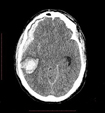

Ematoma

sottodurale acuto ed intraparenchimale |

Traumatologia

cranica |